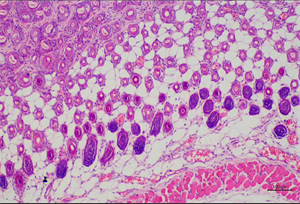

MHIL-200倒置生物显微镜是专为活体细胞观察设计的专业设备,适用于生物切片、活体细胞培养等样本的动态观察,尤其适合贴壁细胞的长时间成像需求。采用无限远光学系统,不同物镜搭配,可实现明场/相衬/荧光观察,效果可以媲美进口品牌;支持多色同步成像;仪器放大倍数可达40-960X。

其模块化设计支持荧光(双色BG和三色BGU波段定制)、相差等功能扩展,三目镜筒可连接数码相机,广泛应用于细胞培养、医疗检验、病理诊断、药物筛选及荧光标记实验等领域,具有操作便捷、成像清晰和性价比高的特点。